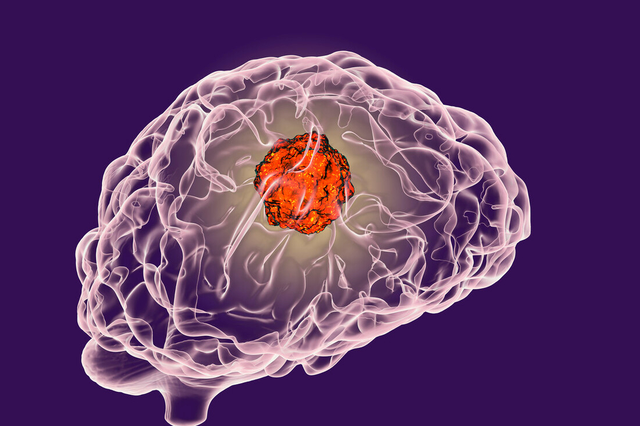

众所周知,大脑是人体重要组成器官之一,拥有一个健康的大脑尤为重要但它也会生病,今天带大家了解,严重的脑部疾病之一——脑肿瘤。他是潜伏很深、演技爆表的最强“伪装者”。如果您不能发现它留下的“蛛丝马迹”,可就要深受其害了。

脑瘤是发生在大脑的肿瘤,包括起源于神经系统的肿瘤,还有其他部位肿瘤发生了脑部导致的脑转移瘤。不一定都是恶性肿瘤,其他如脑膜瘤、垂体瘤、神经鞘瘤、颅咽管瘤等良性肿瘤,治疗效果均非常好,且极有可能治愈。因此,发现脑瘤后,不要自乱阵脚,自暴自弃,积极配合医生治疗才是正确的做法。那么在早期的时候,该如何发现脑肿瘤的“蛛丝马迹呢”?

治疗脑肿瘤的方法有很多,主要包括手术治疗、化疗、智慧精准放疗、靶向治疗、靶向肿瘤干细胞治疗等,也包括影像技术在医学上的应用。许多患者在治疗脑部肿瘤的时候会先选择M6射波刀智慧精准放疗。这是因为射波刀放疗可以不用开刀,能够精准治疗,治疗的效果也比较好。

M6射波刀可以达到亚毫米精度,能短时间内对颅内肿瘤进行控制,并对肿瘤实施精准照射,不仅对肿瘤的杀伤力更强,而且周围正常脑组织接收的剂量低。

相比常规放疗,M6射波刀更高效。如果采用常规放疗治疗恶性胶质瘤,则需要照射27~30次,历时5~6周左右才能完成治疗。但采用M6射波刀照射恶性胶质瘤,一般只需要照射3~5次,一周内即可完成治疗。

脑肿瘤对人体危害极大,及时预防脑瘤的第一件事情就是要注意饮食及作息规律、学会自我纾解压力,减少对大脑的刺激。当自身出现上述异常时,必须立刻就医进行相关检查。如若确诊,应谨遵医嘱,积极配合治疗,尽可能地减少病症对大脑的损伤。只有越早治疗,生存率才会越高。